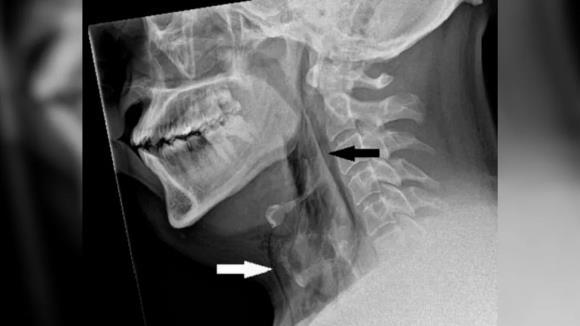

재채기를 참은 한 영국 남성이 기도가 파열돼 목 피부 아래에 공기주머니가 갇힌 것이 확인됐다. 영국 의학 저널(British Medical Journal)

그는 호흡과 삼키기, 말하는 것에는 전혀 문제가 없었다. 의료진이 엑스레이(X-ray)를 촬영한 결과 피부 아래 가장 깊은 조직층 아래에 공기가 갇히는 질환인 폐기종의 징후를 발견했다.

CT 스캔 결과 A씨 목의 세번째와 네번째 뼈 사이에 찢어짐이 생겨 기도에서 공기가 빠져나와 목 조직과 폐 사이 공간으로 들어간 것으로 나타났다. 기도에 생긴 구멍의 크기는 지름 2㎜였다.